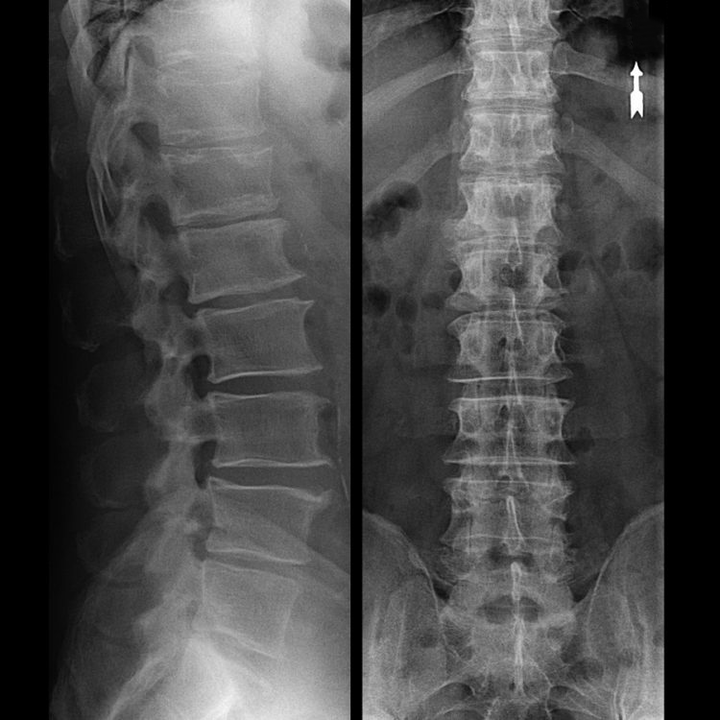

Una “radiografia” del rachide cervicale, e anche con test funzionali di flessione ed estensione, non mostra cartilagine, poiché il suo tessuto trasmette raggi X. Nonostante ciò, in base alla posizione delle vertebre, si possono trarre conclusioni generali sull'altezza dei dischi intervertebrali, sul generale raddrizzamento della curvatura fisiologica del collo - lordosi, nonché sulla presenza di escrescenze marginali sulle vertebre con irritazione prolungata delle loro superfici da parte di dischi intervertebrali fragili e disidratati. I test funzionali possono confermare la diagnosi di instabilità del rachide cervicale.

Poiché i dischi stessi possono essere visti solo mediante TC o MRI, la risonanza magnetica e la tomografia computerizzata a raggi X sono indicate per chiarire la struttura interna della cartilagine e formazioni come protrusioni ed ernie. Pertanto, con l'aiuto di questi metodi, viene effettuata una diagnosi accurata e il risultato della tomografia costituisce un'indicazione, e persino una guida topica, per il trattamento chirurgico dell'ernia nel reparto di neurochirurgia.